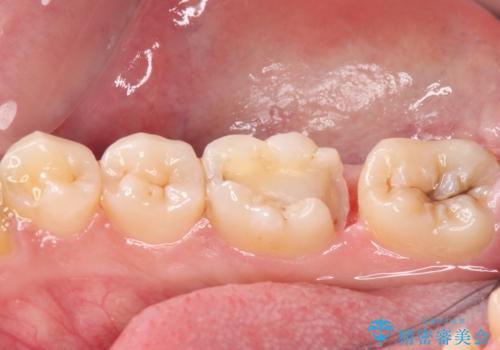

適合の良いセラミック治療は、むし歯再発のリスクが低いです。

目立つ銀歯がなくなり、患者様は大変満足されました。